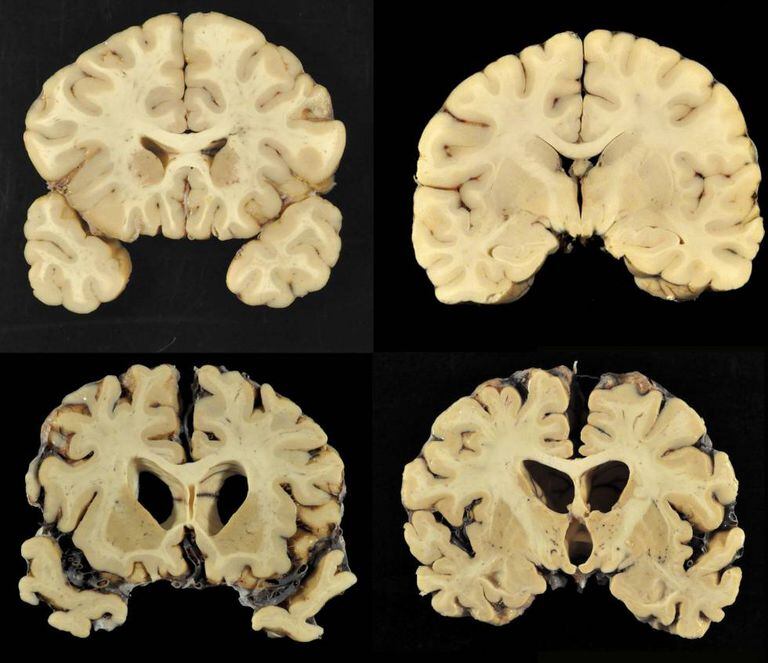

O consenso crescente sobre os danos neurológicos em longo prazo produzidos pelo futebol americano recebeu um novo apoio nesta terça-feira. Um estudo publicado no Journal of American Medical Association constatou lesões cerebrais em 110 de 111 cérebros doados por ex-jogadores da NFL, a liga profissional norte-americana. Embora as conclusões não possam ser extrapoladas para todos os praticantes do esporte mais popular nos Estados Unidos, é a maior amostra estudada até hoje.

A doença conhecida como Encefalopatia Traumática Crônica (ETC) é uma enfermidade degenerativa relacionada com choques na região da cabeça. Também é conhecida como demência pugilística porque começou a ser estudada como uma consequência do boxe. A discussão sobre sua relação direta com a prática do futebol americano começou há pouco mais de uma década como consequência de um estudo envolvendo ex-jogadores com problemas mentais depois da aposentadoria. As consequências podem surgir anos depois dos choques.

No total, o estudo examinou 202 cérebros de pessoas mortas que jogaram em alguma categoria do futebol americano, da escola à NFL, depois dos anos 60. A ETC está presente em 87% deles, 177. Entre aqueles que chegaram a jogar como profissionais, a proporção é superior a 99%. Em alguns casos, os pesquisadores tinham apenas o cérebro. Nos mais recentes, também dispunham de entrevistas sobre o comportamento geral da pessoa e outro tipo de experiências com possíveis consequências traumáticas, como ter estado no Exército.

O estudo encontrou evidências de ETC em 21% dos 14 que tinham jogado na escola, em 91% dos 54 que jogaram na universidade, em 64% de uma amostra de 14 que jogaram como semiprofissionais e em 7 dos 8 que atuaram na liga canadense.